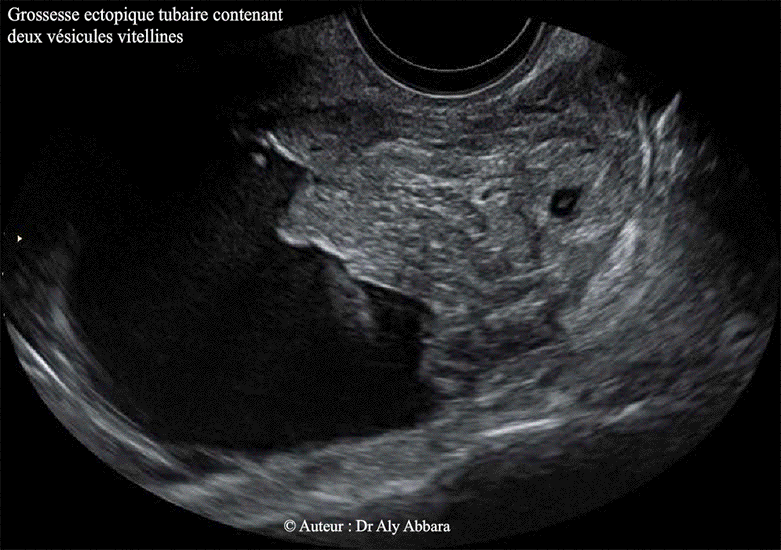

| 24 heures plus tard : apparition au sein de l'amas trophoblastique d'une cavité

chorionique (cœlomique externe) contenant deux vésicules vitellines Taux de hCG plasmatique est de 1850 UI/l |

Ces images échographiques illustre un cas de grossesse extra-utérine tubaire gauche caractérisée par la présence d'un sac gestationnel formé d'une couronne trophoblastique entourant une cavité chorionique (cœlomique externe) contenant deux vésicules vitellines (vésicules ombilicales) ; donc il s'agit d'une grossesse ectopique tubaire, gémellaire débutante, monochoriale bi-amniotique. |